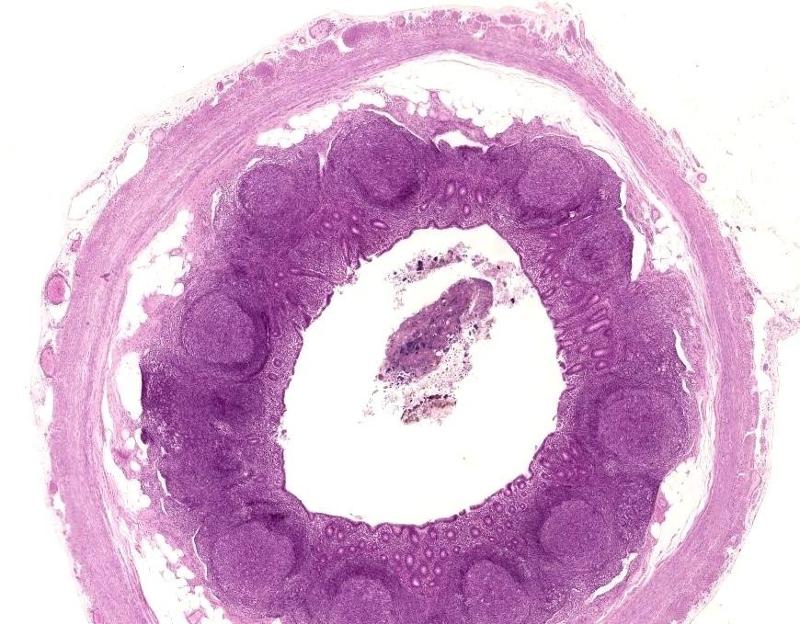

Эпителий слизистой оболочки червеобразного отростка - фото презентация